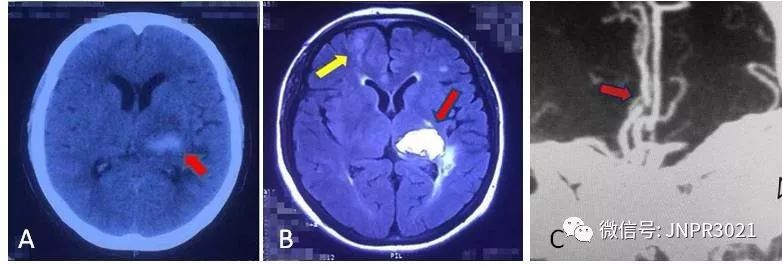

上图A 首次发病时颅脑CT篇,红色箭头指示为脑出血病灶;图B 卒中复发颅脑MRI片,红色箭头指示原来的脑出血病灶,黄色箭头指示为新发脑梗死病灶;图C 脑血管造影图片,红色箭头示左大脑前动脉重度狭窄。